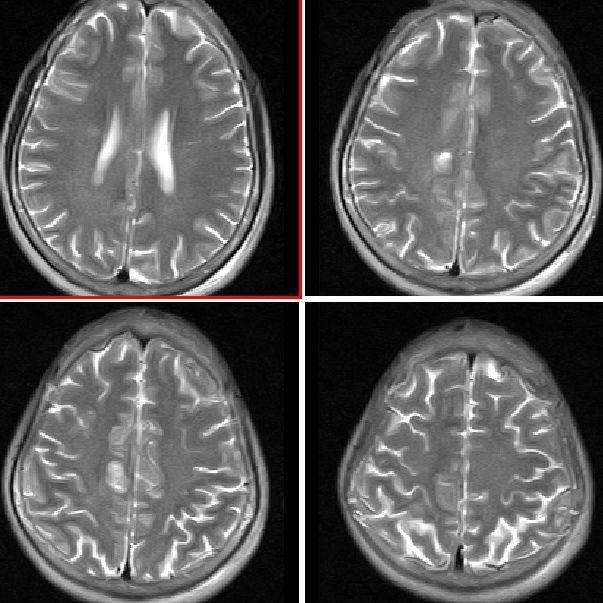

mri平扫

mr表现:中央旁小叶区病灶号不均匀性稍长t1、长t2信号,病灶周边见稍短t1信号环。右侧脑室体旁见点片状等t1、稍长t2信号影。flai序列各病灶均呈高信号。增强后右侧中央旁小叶区病灶呈不均匀性强化。